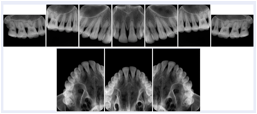

3. A dental provider wishes to capture a series of DICOM IO images for the patient’s dentition. The tooth morphology, teeth are divided into molars, premolars, canines and incisors, and a number of images for each jaw. The anatomic information was captured utilizing the triplet of schema. This standard code sequence is based on ISO 3950-2010, Dentistry - Designation system for teeth and areas of the oral cavity.

Every IO image should have anatomic information either through the primary or modifier sequence.

In most standard cases, images are oriented in structured layouts. These structured displays are useful to be shared between providers for reference purposes.

Table OO.1.1-1 shows structured display standard templates, where Viewset ID is based on the Japanese Society for Oral and Maxillofacial Radiology (JSOMR) classification provided by JIRA (Japan Medical Imaging and Radiological Systems Industries Association, www.jira-net.or.jp). Expected or typical teeth to be imaged location, region and designation codes are based on ISO 3950-2010, Dentistry - Designation system for teeth and areas of the oral cavity. For all the hanging protocols listed in OO.1.1-1, the value to use for Hanging Protocol Creator (0072,0008) is "JSOMR" and the value to use for Hanging Protocol Name (0072,0002) does not include "JSOMR" (e.g., "DL-S001A", not "JSOMR DL-S001A").